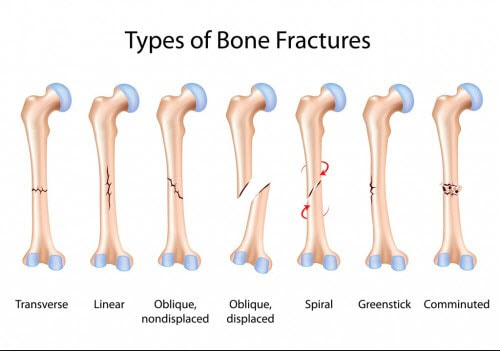

Jenis Dan Kategori Tulang Patah

Jenis Dan Kategori Tulang Patah

Topik 4 sains sukan

Fraktur - Jenis û Penyebab dan Pengobatan - IDN Medis

Fraktur - Jenis û Penyebab dan Pengobatan - IDN Medis

Bab 5 luka & patah

Bab 5 luka & patah

Sering Dialami Atlet, Ini 7 Perbedaan Patah Tulang dan Dislokasi

Sering Dialami Atlet, Ini 7 Perbedaan Patah Tulang dan Dislokasi

Ini yang Dimaksud dengan Fraktur Tulang

Ini yang Dimaksud dengan Fraktur Tulang